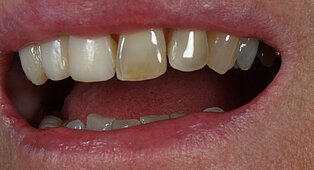

Vom Langzeitprovisorium zur TEK 1 Arbeit